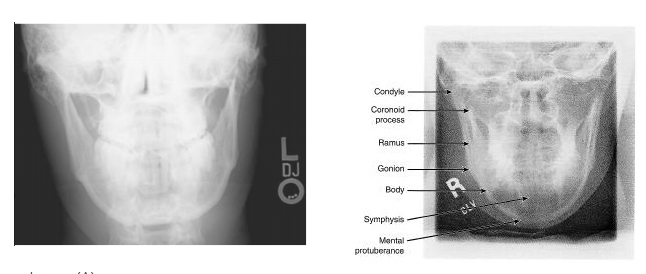

To demonstrate the mandibular body in the PA position, the

A - CR is directed perpendicular to the IR.

B - CR is directed cephalad to the IR.

C - skull is obliqued away from the affected side.

D - skull is obliqued toward the affected side.

A

The straight PA projection (0 degrees), with the central ray directed perpendicular to the IR, effectively demonstrates the mandibular body. In this position, the rami and condyles are superimposed on the occipital bone and petrous portion of the temporal bone. To better visualize the rami and condyles, the central ray is directed cephalad 20 to 30 degrees.

With the patient's head in a PA position and the CR directed 20 degrees cephalad, which part of the mandible will be best visualized? A - Symphysis B - Rami C - Body D - Angle

B - Rami With the patient in the PA position, the rami are well visualized with a perpendicular ray or with 20 to 25 degrees of cephalad angulation. A portion of the mandibular body is demonstrated in this position, but most of it is superimposed over the cervical spine.

Which of the following structures is illustrated by the number 2 in Figure 2–21? A - Maxillary sinus B - Coronoid process C - Zygomatic arch D - Coracoid process

C - Zygomatic arch The parietoacanthial projection (Waters method) demonstrates a distorted view of the frontal and ethmoidal sinuses. The maxillary sinuses (number 4) are well demonstrated, projected free of the petrous pyramids. This is also the best single position for the demonstration of facial bones. The mandibular angle is illustrated by number 1, the zygomatic arch by number 2, and the coronoid process by number 3.

What should be done to better demonstrate the mandibular rami seen in PA projection in Figure A? A - use a perpendicular CR B - angle the CR cephalad C - angle the CR caudad D - oblique the head 15° medial

B - angle the CR cephalad Figure A shows a PA projection of the mandible. The head is positioned PA with the OML perpendicular to the IR. The mandibular body is well demonstrated in this position. With the patient in the PA position, the rami can be better demonstrated with 20° to 25° cephalad angulation. A caudal angle could be employed if the skull were positioned in the AP position.